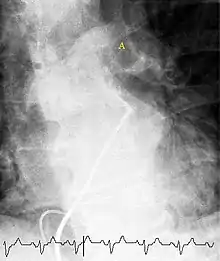

Селективна контрастна ангіопульмонографія

Селективна контрастна ангіопульмонографія дозволяє достатньо точно діагностувати ТЕЛА, проте цей метод є інвазивним, а отже, потенційно небезпечним для обстежуваного. Недоліком обстеження є також можливість алергічних реакцій на контраст та токсична дія препарату на нирки. У хворих високого ризику проведення ангіографії не рекомендується, оскільки підвищує ймовірність кровотечі після тромболітичної терапії (ТЛТ). Використання ангіографії може бути корисним, якщо результати неінвазивних методів обстеження виявились суперечливими. Якщо при сцинтиграфії було знайдено неспецифічні порушення перфузії, доцільне проведення селективної ангіографії певних ділянок. Це дозволяє зменшити кількість рентгенконтрастної речовини, яка вводиться при ангіографії, що дозволяє зменшити імовірність побічних ефектів обстеження. При обстеженні у хворих з ТЕЛА при селективній ангіопульмонографії критеріями встановлення діагнозу можуть служити дефект наповнення просвіту судини, повна обтурація судини («ампутація» судини, обрив її контрастування з розширенням проксимальніше місця оклюзії). До непрямих критеріїв ТЕЛА зараховують розширення головних легеневих артерій, зменшення кількості контрастованих периферичних гілок — симптом «мертвого чи підрізаного дерева», деформацію легеневого малюнка, відсутність чи затримку венозної фази контрастування, асиметрію заповнення судин контрастною речовиною.[14]